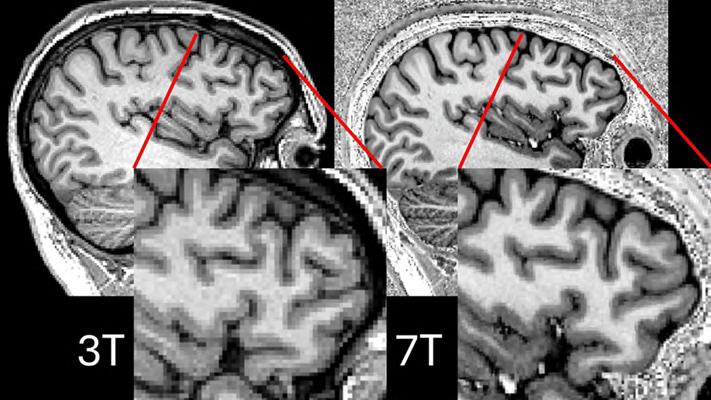

Ultra-Powerful MRI Scans Enable Life-Changing Epileptic Surgery

Image: Comparison showing 3T and 7T scans for the same participant (Photo courtesy of P Simon Jones/University of Cambridge)

Researchers from the University of Cambridge’s Wolfson Brain Imaging Centre (Cambridge, UK; www.wbic.cam.